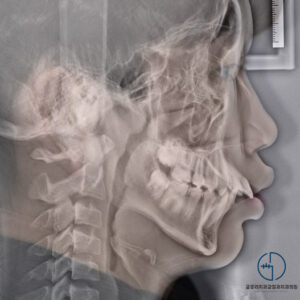

중화동 치과 윗니가 아랫니를 너무 깊게 물어요. 전치부 과개교합(deep bite) 개선 증례

안녕하세요, 여러분~ 중화동 글로리 치과 김정은 원장입니다. ​ 날이 가면 갈수록 점점 더워지고 있네요. 봄이 온지 얼마 지나지 않은 것 같은데 벌써 여름이 찾아오고 있나 봅니다. ​ 지난번에 반대교합에 관련된…